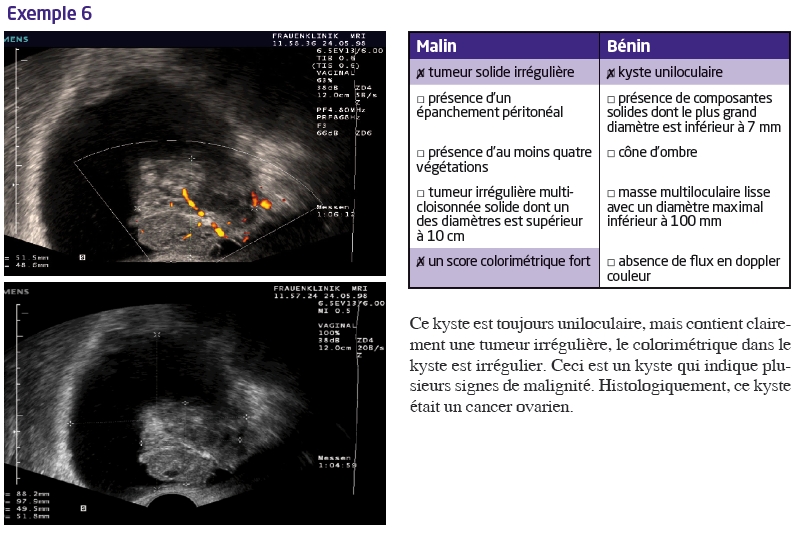

En utilisant les règles de Timmerman, la distinction entre un kyste bénin ou une tumeur maligne est simplifiée. Prenons quelques exemples :

5 règles pour «malignité»

- tumeur solide irrégulière

- présence d’un épanchement péritonéal

- présence d’au moins quatre végétations

- tumeur irrégulière multi-cloisonnée solide dont un des diamètres est supérieur à 10 cm

- score colorimétrique fort.

5 règles pour «bénignité»

- kyste uniloculaire

- présence de composantes solides dont le plus grand diamètre est inférieur à 7 mm

- cône d’ombre

- masse multiloculaire lisse avec un diamètre maximal inférieur à 100 mm

- absence de flux en doppler couleur.